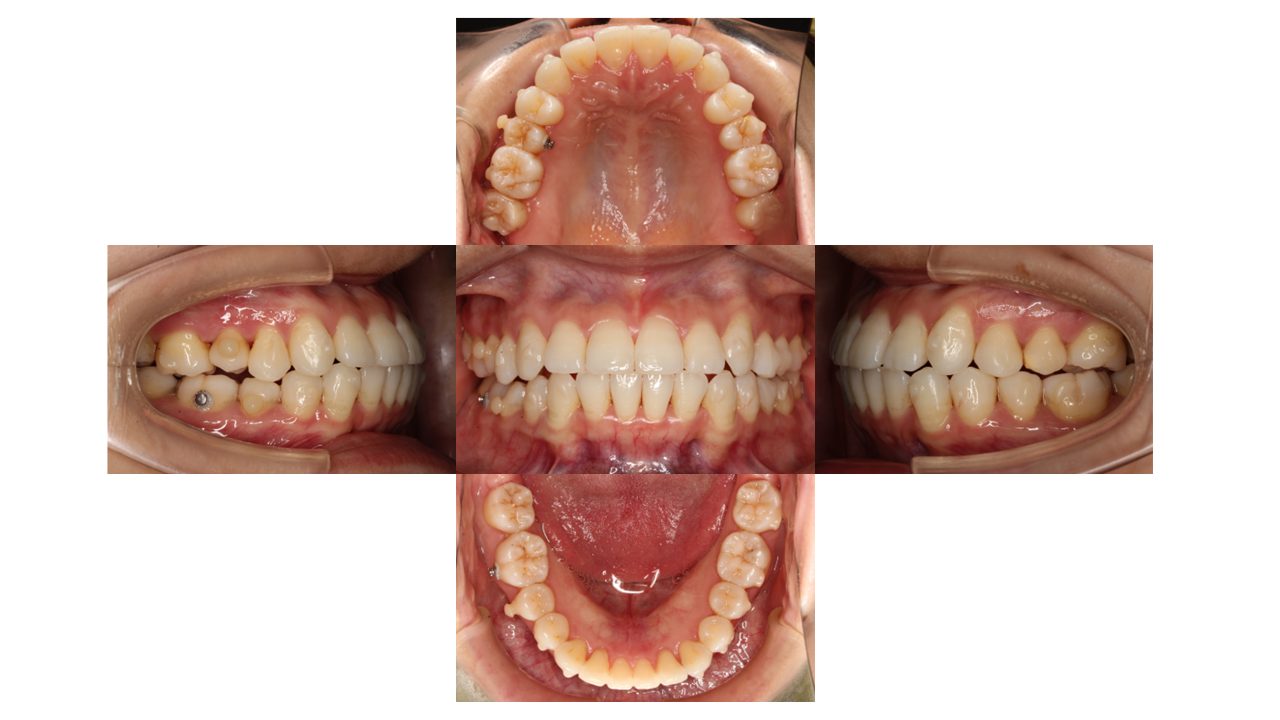

9カ月経過の口腔内の状態です。

歯の表面には、「アタッチメント」という突起がついています。

アタッチメントには、歯とマウスピースのフィットを良くし、歯の動きを助ける役割があります。

右側にはボタンを装着し、マウスピースに加え、顎間ゴムも併用していただきます。